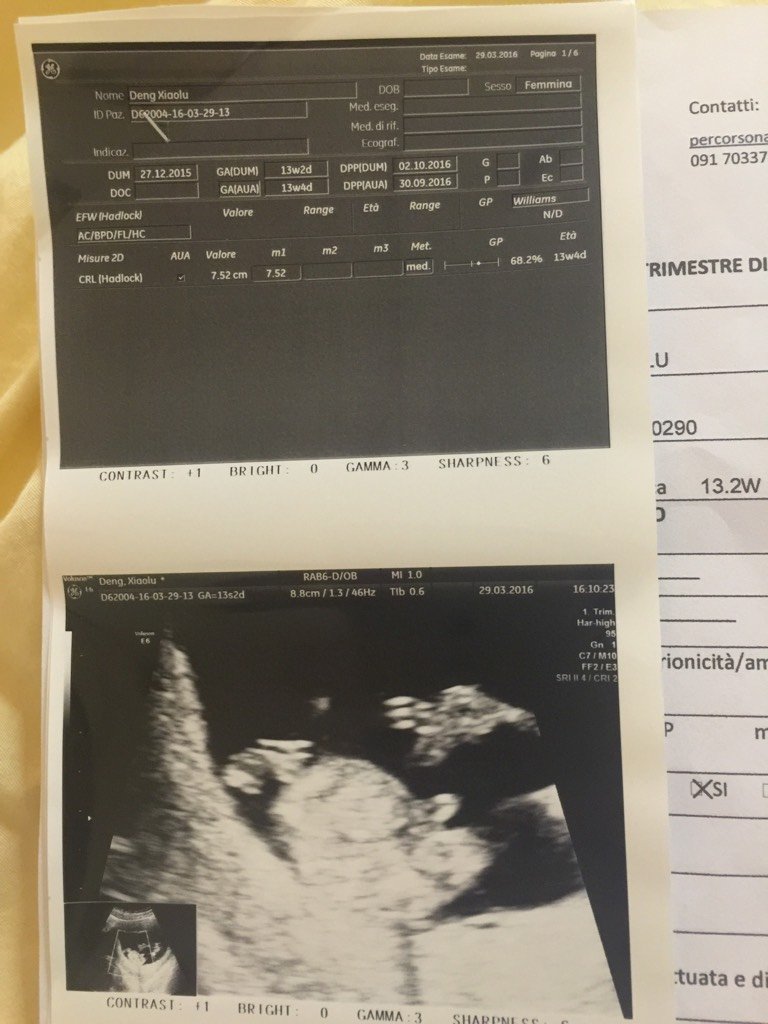

去医院做了B超一切正常,也验血了,也听胎心了!连男女都看清楚了,为什么还总是出血?现在已经孕15周 去医院做了B超一切正常,也验血了,也听胎心了!连男女都看清楚了,为什么还总是出血?现在已经孕15周+5天。请问胚胎宝胶囊能吃吗? 点击展开 露Lucia 2016-04-15 03:59 为您推荐: 其他回答 卧床吧,, 肥妞2 2016-04-15 06:18 问问医生呗 胡广花 2016-04-15 06:14 看看宫口有没有积液 小豌豆m 2016-04-15 06:07 最好去医院咨询下医生 儿女👫双全 2016-04-15 05:50 多休息,保胎吧! 玻璃心啊清 2016-04-15 05:45 加载更多 相关问题 孕12周出血去医院检查验血b超都正常,回来后又流血怎么回事? 怀孕六个月,阴道有出血,B超胎盘低置,脐带绕颈,在医院保胎两周,还是有出血,昊是怎么回事? 我42天的时候去验血,孕酮10 08吃了8天黄体酮,因为没有出血,我没有在去医院化验,现在8周了